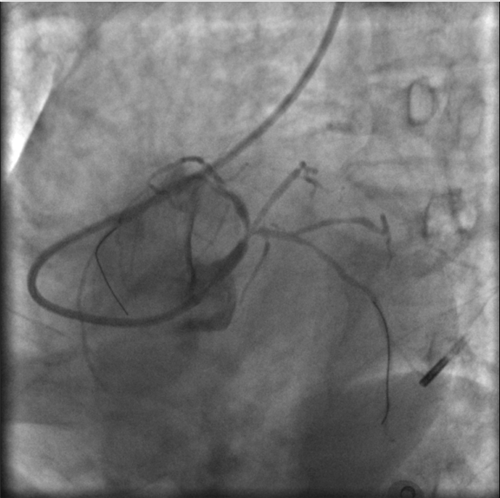

根據IVUS檢查結果,在前降支近中段至左主干植入3枚支架,充分擴張后,狹窄完全解除,血流恢復通暢。

植入3枚支架,血流恢復通暢